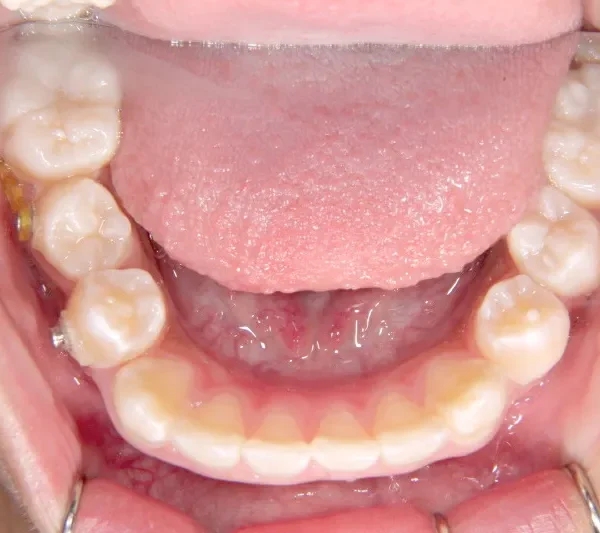

【子供の矯正(一期)】叢生・開咬・前歯で噛めない・舌癖・7歳女児【M.O様】

治療終了後

治療回数31回、4年11ヶ月の治療期間で矯正治療を終了しました。

主訴が改善され、ご満足頂きました。